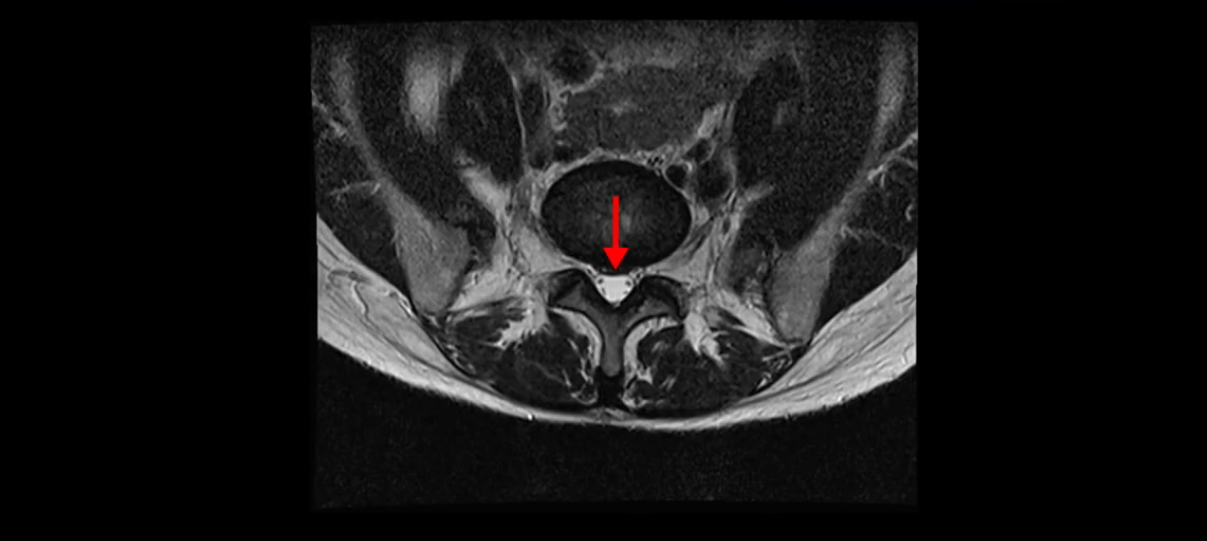

이분 MRI를 보시면 두 마디의 퇴행성디스크가 있습니다. 그리고 디스크가 조금씩 밀려 나와 있고요. 그런데 디스크 탈출 정도는 두 마디 다 심하지 않습니다. 4번 5번에는 디스크 탈출이 약간 있고,

척추관협착도 약간 진행이 되고 있고요.

5번 1번은 디스크 탈출이 가운데 쪽으로 살짝 있습니다.

중요한 것은 이 정도 경미한 탈출과 협착으로는 양쪽 다리가 저리고 아플 수가 없습니다.

그리고 만약에 이 디스크가 급성으로 찢어진 것이라면 아주 심한 디스크성 통증이 있겠죠. 기침이나 재채기를 하면 심하게 아프고 허리를 조금만 구부려도 아주 날카로운 통증들이 생길 겁니다. 그런데 이분은 이런 증상이 전혀 아닙니다. 디스크의 돌출 정도와 협착이 전혀 심하지 않기 때문에 이분이 가지고 계신 양쪽 다리 저림, 특히 이분은 누워있을 때도 양쪽 다리가 저리다고 하는데, 디스크 때문에 그런 증상은 생길 수가 없습니다. 또 이 디스크는 오래된 디스크, 이미 찢어진 섬유륜이 아문 디스크이고, 그러니까 이분은 기침이나 재채기를 못하는 증상이 없는 거죠. 그 다음에 허리를 구부릴 때 뻐근한 증상은 있지만 아주 날카로운 통증은 없습니다.

이분 MRI를 보시면 퇴행성디스크가 있고 약간의 협착이 있지만 이 정도의 퇴행성디스크와 협착으로는 신경이 눌려서 양쪽 다리가 저리고 아픈 증상이 나올 수가 없습니다. 그래서 MRI와 이 환자분의 다리 증상이 매치가 안 된다고 하는 의사들이 많은 겁니다.